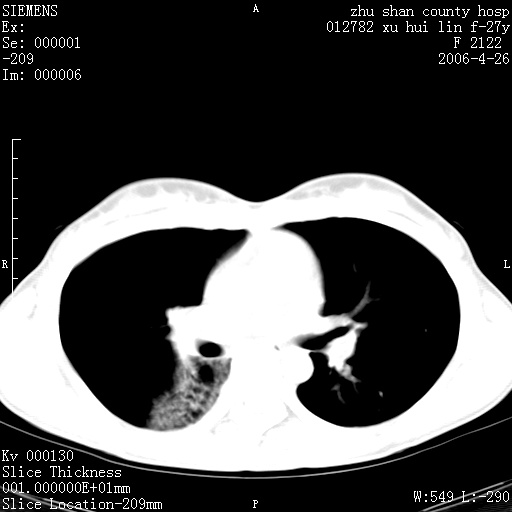

女性 病人 27岁!本院职工家属,五月前因感冒透视发现病变,ct示:左肺下叶背段感染性病变。经过半月规范抗生素治疗后复查病变无明显变化,后行四月规范抗痨治疗,复查无明显变化,后复查无效!请大家帮忙看看!

右肺下叶背段见片状高密度区,边界不清,密度不均,无钙化及空洞影,背段支气管通畅。所见层面肺门及纵隔内未见明显肿大淋巴结影。

女性 病人 27岁!本院职工家属,五月前因感冒透视发现病变,ct示:左肺下叶背段感染性病变。经过半月规范抗生素治疗后复查病变无明显变化,后行四月规范抗痨治疗,复查无明显变化,后复查无效!

诊断:首先还是考虑为慢性炎症。

结核虽然好发于下叶背段,但周围无明显卫星灶,化验结果怎样?